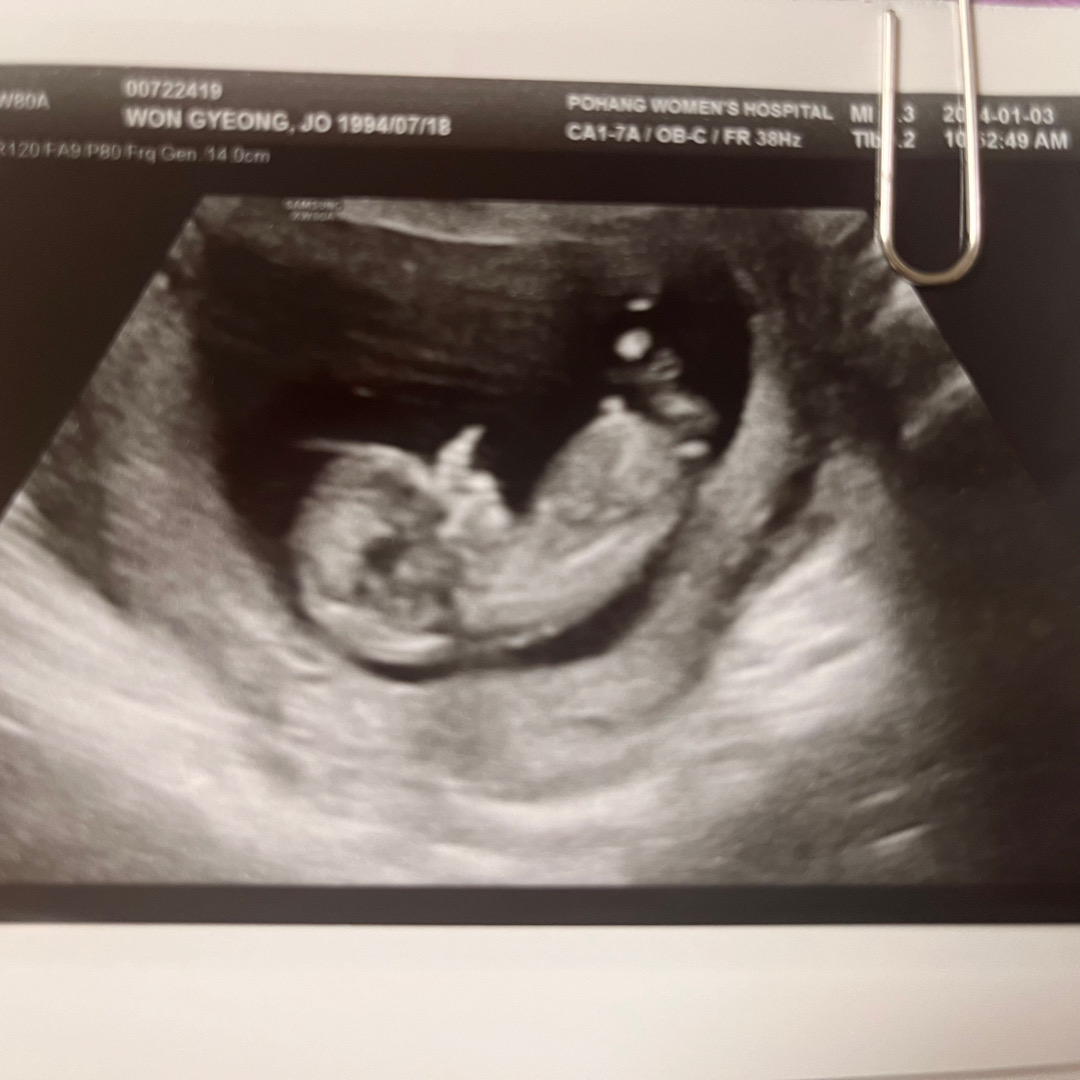

각도법으로 성별한번만 봐주세용

너무궁금한데 추측이안되네요ㅠㅠ

사진이 정확하지는 않은데 딸같아 보여용